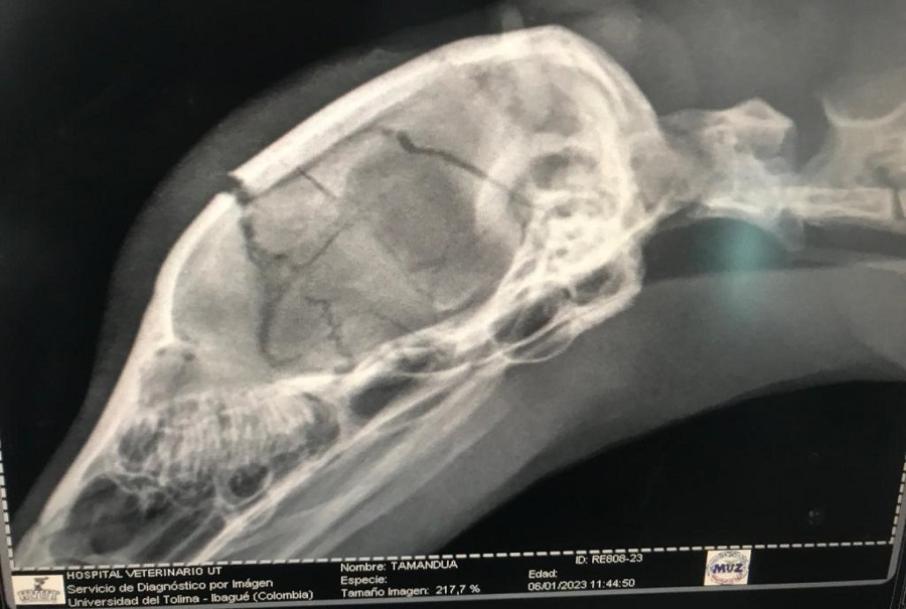

Oso hormiguero murió por un garrotazo en su cabeza

Por la gravedad de las lesiones, el animal no pudo ser salvado pese al esfuerzo de los veterinarios.

La Corporación Autónoma Regional del Tolima, Cortolima, reportó la muerte de un oso hormiguero luego de cinco días de luchar por su vida.

El animal ingresó al centro de Atención y Valoración de Fauna Silvestre, CAV, con una grave lesión en la cabeza, producto de un fuerte golpe que le propinaron.

"A causa de esto, el animal presentó una afectación neurológica y no podía mover sus extremidades superiores. De inmediato los médicos veterinarios, zootecnistas, biólogos y demás profesionales iniciaron el proceso de recuperación para tratar de disminuir la inflamación en el cerebro, además tuvo que ser alimentado por sonda", reporta la autoridad ambiental en un comunicado.